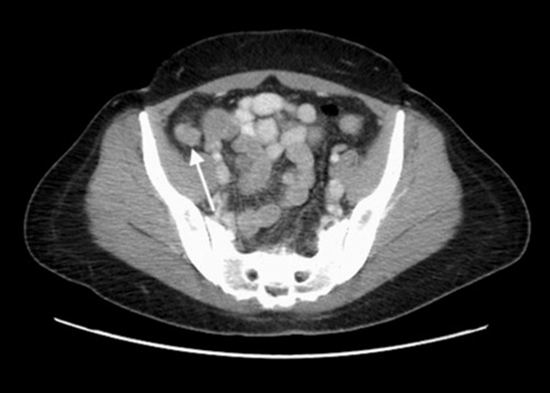

Twenty-six out of the total number of patients who underwent CT (30) had positive findings (86.6%), while 7 out of the total number of patients who underwent MRI (11) and 11 out of the total number of patients who underwent sonography (13) also had positive findings (63.6% and 84.6%, respectively). The mean age of the patients was 37.2 ± 7.07 years. Out of the total sample, 8 patients were pregnant. The overall imaging findings were: Normal (6 cases, 15%), wall thickening (9 cases, 22.5%), mass (15 cases, 37.5%), cystic mass (1 case, 2.5%), solid lesion in the left ovary (1 case, 2.5%), mucocele (3 cases, 7.5%), intussusception (4 cases, 10%), obstruction (5 cases, 12.5%), suspected obstruction (1 case, 2.5%), appendicitis (4 cases, 10%), fluid (11 cases, 27.5%), and abscess (3 cases, 7.5%). Conclusion:

Right lower quadrant (RLQ) mass and bowel wall thickening are the most commonly reported findings in patients with AE. Further studies are required to retrospectively evaluate the imaging findings of the appendix in pathologically confirmed AE after pelvic surgery